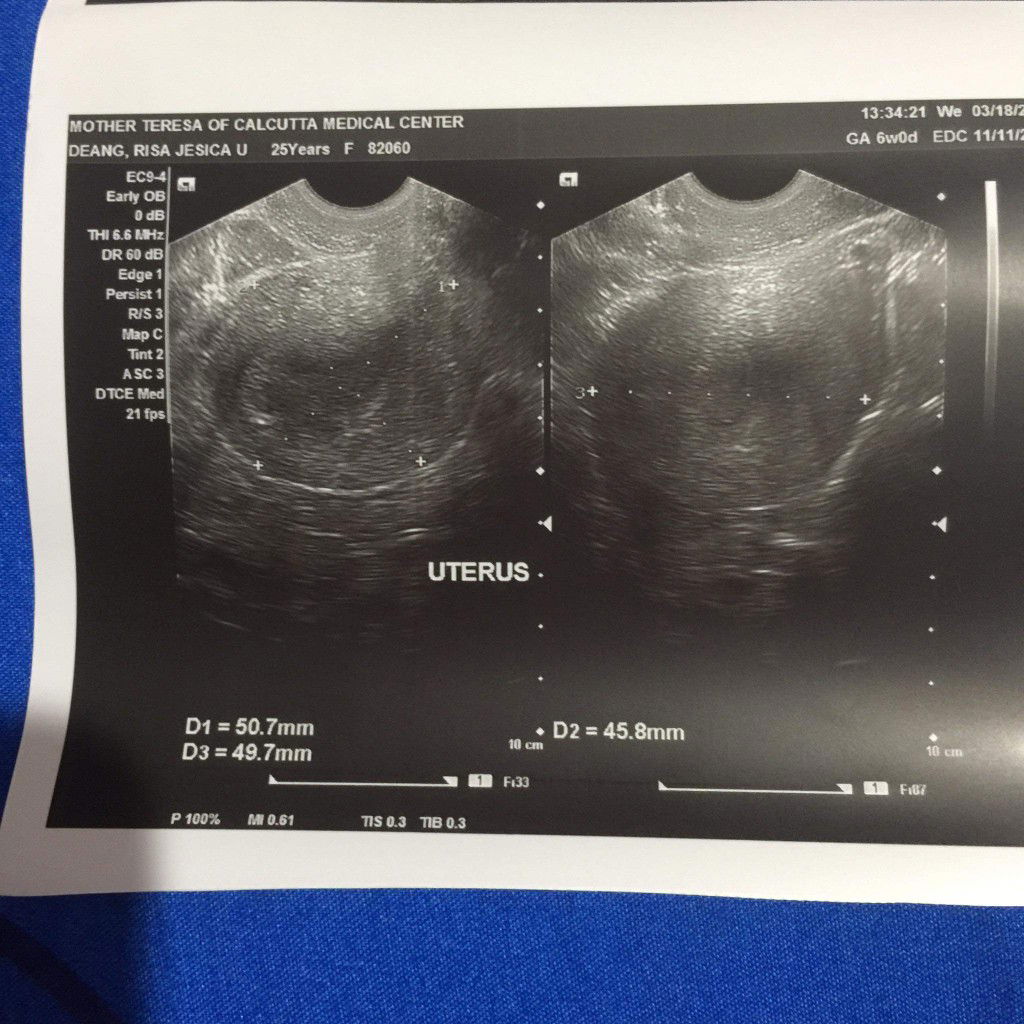

6weeks preggy

..March 16 morning positive 2 pt. May pain side ng puson sobra sakit at nag pa er. March 16 8pm spotting 3days yun bed rest. Take duvadilan that night n nex morning. Nag txt sa ob req TVS March 17 TVS done. Wala GS sac wala pa heartbeat baby pina stop duvadilan. BED REST March 20 2pm sumakit pusun parang pag nag mmens ako. Tapos bleeding flow panag pperiod. Till now March 21 morning (ready na) nag PT ulit kc nag wworry mens na itsura na blood. NEGATIVE na po 2 pt. Galing na dn ng ob failed pregnancy dw. ? Ps. march 20 night iniyak ko na lahat kc ramdam ko na wala na. Kc sa flow ng blood na lumlabas.

6weeks n 1 day

March 16 morning positive 2 pt. May pain side ng puson sobra sakit at nag pa er. March 16 8pm spotting 3days yun bed rest. Take duvadilan that night n nex morning. Nag txt sa ob req TVS March 17 TVS done. Wala GS sac wala pa heartbeat baby pina stop duvadilan. BED REST March 20 2pm sumakit pusun parang pag nag mmens ako. Tapos bleeding flow panag pperiod. Till now March 21 morning (ready na) nag PT ulit kc nag wworry mens na itsura na blood. NEGATIVE na po 2 pt. Galing na dn ng ob failed pregnancy dw. ? Ps. march 20 night iniyak ko na lahat kc ramdam ko na wala na. Kc sa flow ng blood na lumlabas.

6weeks pregnant today

Mejo natatakot ako nag pa ultrasound tapos wala makita Gestational Sac. Baka dw early pregnancy. Pls pray for me n my baby